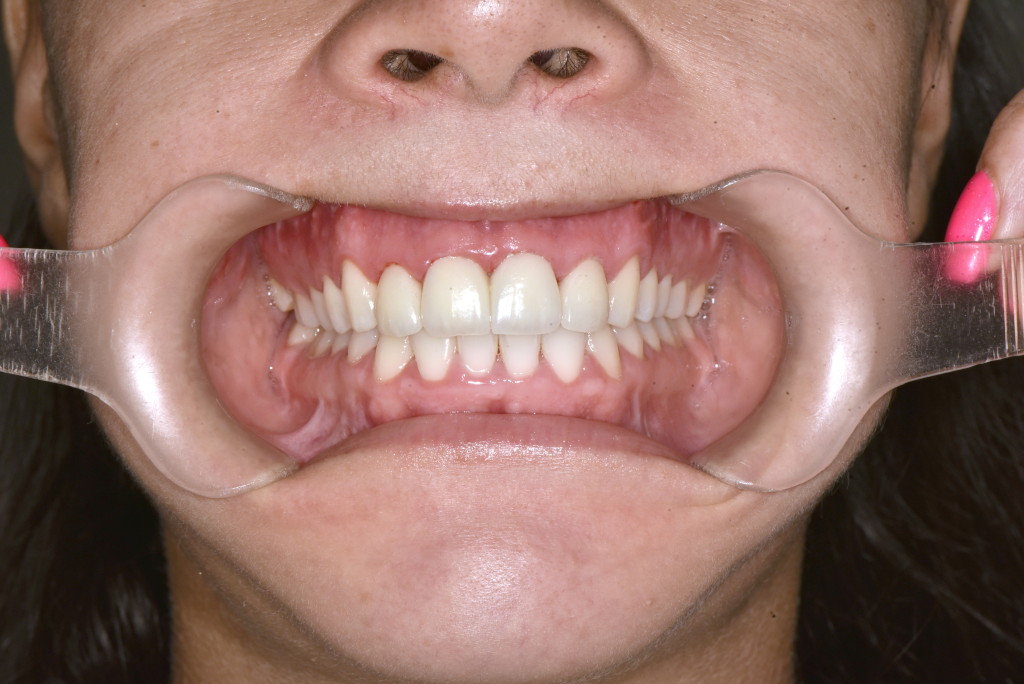

Utána fogsor - Ínymosoly műtéti megoldása​

Az ínymosoly ebben az esetben nem pusztán esztétikai kérdés volt.

A felső állcsont függőleges túlnövekedése és az alsó állkapocs helyzete együtt bontotta meg az arányokat.

A kezelést fogszabályozással készítettük elő, majd kétállcsontos állcsontműtétet végeztünk.

A felső állcsont pozíciójának módosításával csökkent az ínyláthatóság,

az alsó állkapocs korrekciója pedig stabil harapást eredményezett.

Eredmény: kevesebb íny, harmonikusabb arcprofil, hosszú távon stabil funkció..